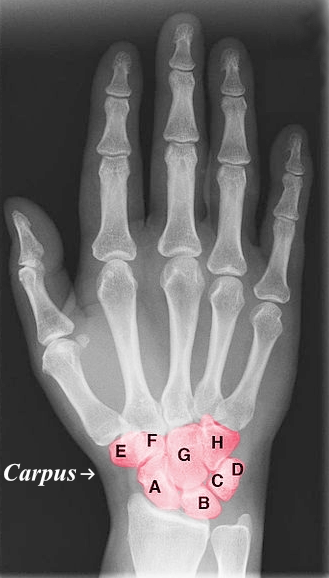

Letter A

Scaphoid

Letter B

Lunate

Letter C

Triquetrum

Letter D

Pisiform

Letter E

Trapezium

Letter F

Trapezoid

Letter G

Capitate

Letter H

Hamate